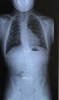

側弯の方はこのように歪んでいる状態です「小学生から来ている子が高校生に✨ 」

側弯の方はこのように歪んでいる状態です

皆さん側弯と言う言葉を知っていますか?

背骨って前から見たら当たり前に真っ直ぐ、な人ばかりではありません

歪みを持つ人、お子さんも大人も居ます

その中の1人で小学生から見ていたお子さんも、この春高校生に☘️

病院でも経過観察しながら、kcsの施術も受けながら、成長されました

直近のレントゲンも歪みは進んでおらず、ピーク時よりとても綺麗です🤩